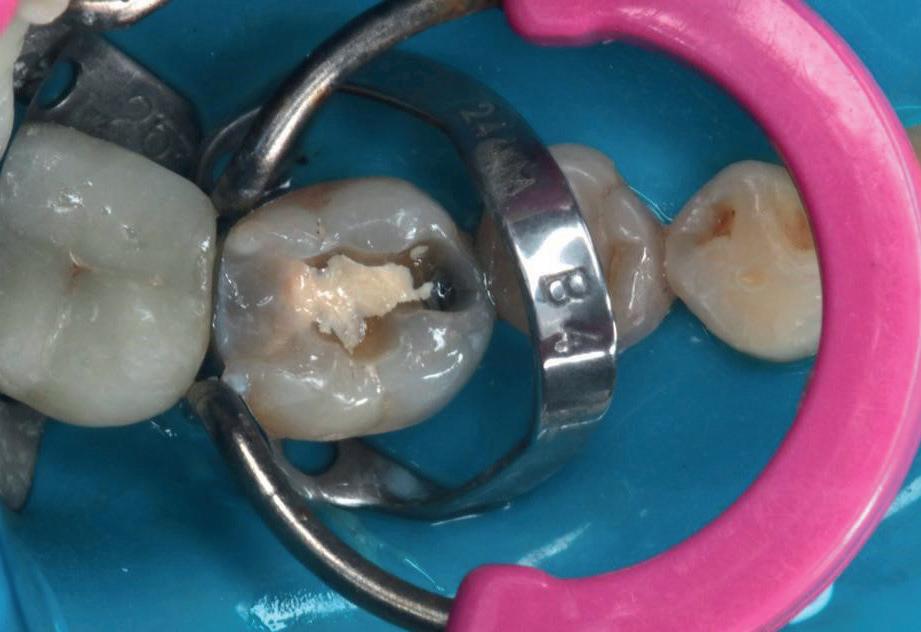

Planul de tratament a început cu accent pe restabilirea sănătății parodontale. Într-o ședință ulterioară, odată cu îmbunătățirea stării parodonțiului, s-a efectuat restaurarea molarului nr. 46. Sub anestezie la Spina Spix pe partea dreaptă și

Figurile:

3. Cavitate de clasa a II-a preparată.

4. Septomatrix pe poziție.

5. Cavitatea profundă.

izolarea cu digă de cauciuc, restaurarea din amalgam a fost îndepărtată complet și s-a obținut accesul la cavitatea carioasă (fig. 3-5). În ciuda proximității față de țesutul pulpar, nu a avut loc nicio expunere, iar cavitatea de clasa a II-a a fost restaurată complet cu Biodentine™ (fig. 6-8).